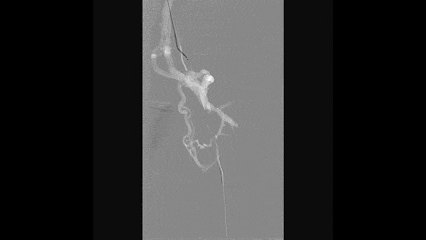

术后造影显示:

左侧股深静脉到左侧髂外及髂总静脉全程通畅

侧支循环消失

形态良好,无明显狭窄,管腔通畅